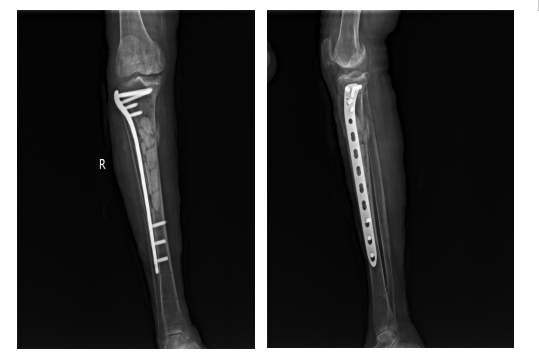

术后恢复良好,按计划于20229月实施第二步治疗方案:再次清创+抗生素骨水泥髓腔内填充术+去除外固定支架更改为钢板内固定

为什么负压引流【前沿技术】负压封闭引流联合Masquelet技术治疗“不死癌症”——骨髓炎_https://www.jmylbn.com_新闻资讯_第6张